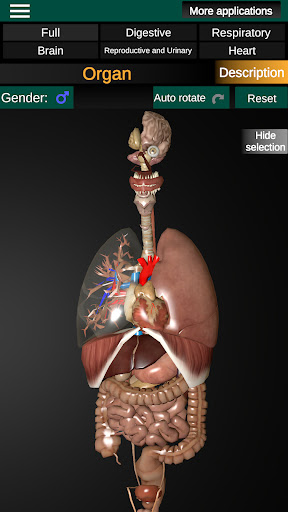

Menampilkan model anatomi 3D dari organ utama tubuh manusia dan penjelasannya masing-masing.

* Sistem pencernaan, termasuk lambung, usus kecil, usus besar, dan animasi sistem ini.

* Sistem pernafasan, yang meliputi trakea, bronkus, paru-paru dan animasi sistem ini.

* Sistem reproduksi, yang meliputi organ reproduksi pria dan wanita.

* Bandingkan organ pria dan wanita.